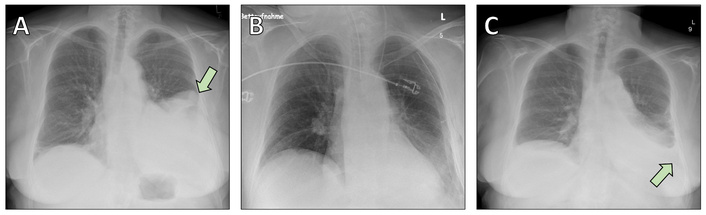

A 69-year-old woman with a history of pustular psoriasis on long-term corticosteroid therapy and a 20-pack-year smoking history presented with progressive exertional dyspnea. An SFT of the left lower lobe had been diagnosed by computed tomography (CT)-guided biopsy four years earlier, but surgery was initially deferred. Follow-up imaging showed marked tumor growth to approximately 15 × 14.5 × 12.5 cm (Figure 1, Figure 2A), leading the multidisciplinary tumor board to recommend resection.

Chest radiographs obtained during the perioperative period. (A) Preoperative chest X-ray showing a large opacity corresponding to the solitary fibrous tumor in the left lower lobe (arrow). (B) Postoperative chest X-ray demonstrating satisfactory re-expansion of the remaining lung parenchyma following left lower lobectomy. (C) Postoperative image revealing a pleural effusion (arrow), which was successfully managed with conservative treatment using diuretics.

The patient underwent open left lower lobectomy with mediastinal lymphadenectomy (Figure 2B, Figure 3). She was extubated on the day of surgery but developed cardiopulmonary instability requiring re-intubation and cardiopulmonary resuscitation. She recovered with supportive care and was successfully extubated on postoperative day 5. A postoperative CT scan revealed a small peripheral pulmonary embolism in the right upper lobe artery; anticoagulation with apixaban was started. Postoperative histology confirmed the diagnosis of SFT (Figure 4).

Her subsequent course was marked by transient tachyarrhythmia managed with digoxin, effective diuresis, and empiric antibiotics for elevated inflammatory markers. Thoracic drains were removed uneventfully, and she was transferred to the surgical ward on postoperative day 12. She reported moderate chest pain attributed to resuscitation efforts, but cardiac ischemia was excluded. A postoperative pleural effusion (Figure 2C) was treated with diuretics.